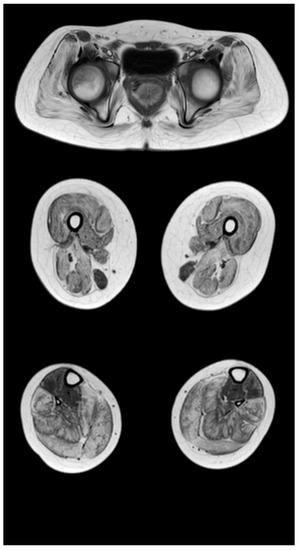

Figure 4.

Pattern of involvement of the muscles of the lower extremities in a patient at the late outpatient stage of the disease (9.4 years). From top to bottom: the pelvic level, the femoral level, and the level of the legs.

At the late outpatient stage, the muscles of the pelvic girdle are characterized by heavy fat substitution of the gluteus maximus and middle muscles (stages 3 and 2b), as well as the muscles straining the fascia lata of the thigh (stage 2b), while the long and short adductor muscles are preserved (Figure 4). In the thighs, progressive fibro-fatty degeneration of the adductor muscles (stage 3), the biceps femoris (stage 2b on the right and stage 2a on the left), semitendinosus, semimembranosus, and quadriceps femoris muscle (stage 2a) is visualized. Thin and sartorius muscles at this stage are characterized by minimal changes or complete preservation (0–1 stages). At the late outpatient stage, the legs are characterized by a pronounced progressive lesion of the long peroneal muscles (stage 3) and of the medial and lateral heads of the gastrocnemius muscles (stage 2a).